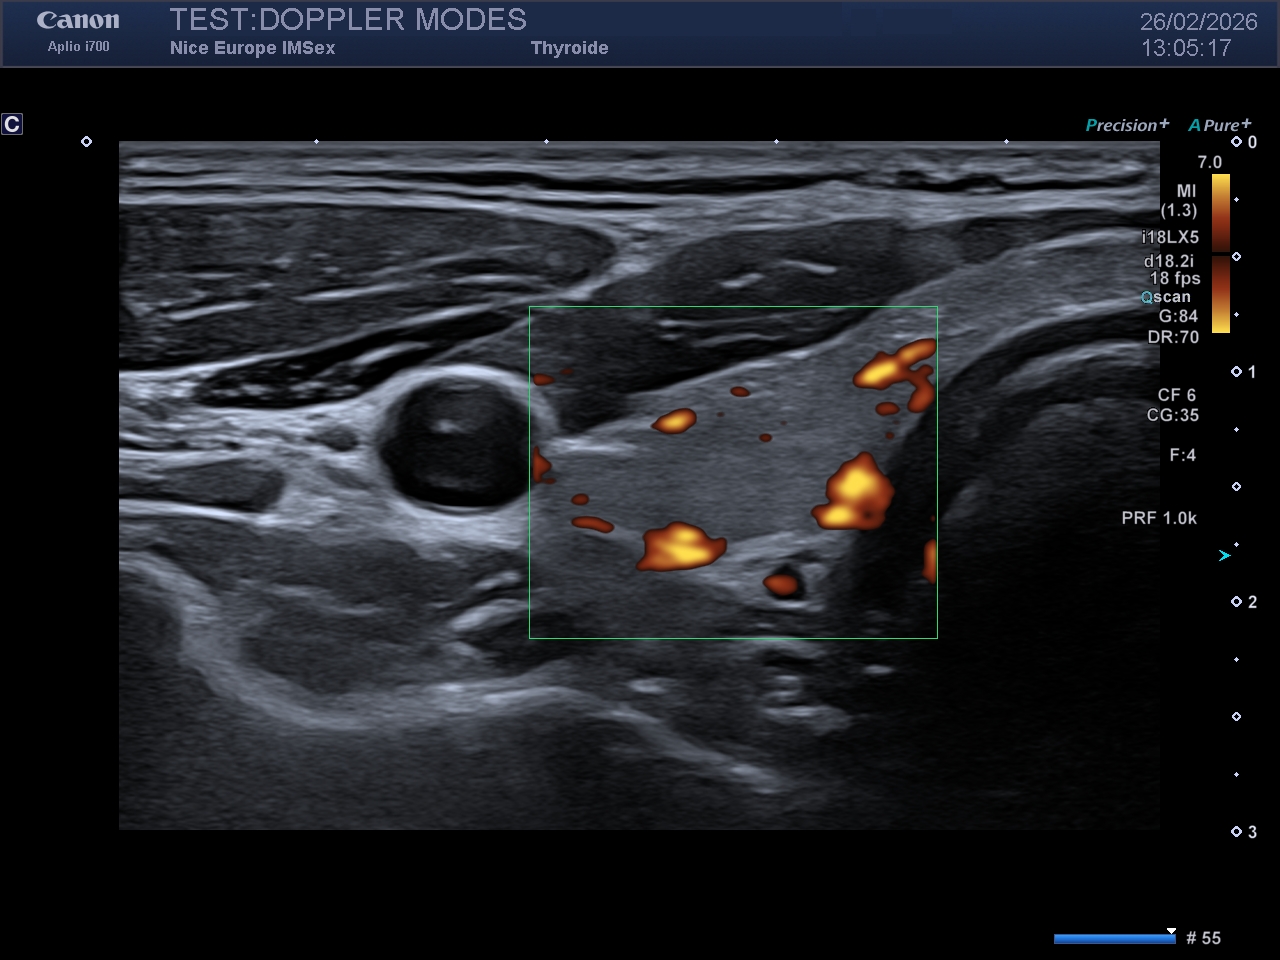

Légende : Image en Doppler Énergie du même rein droit. Notez la plus grande quantité de signal Doppler affichée sur l'image, mais aussi le caractère "grossier" de la cartographie couleur

Le Doppler Énergie a été développé pour répondre à ces deux limites du Doppler couleur. Dans ce mode, l'échographe ne va pas chercher à calculer puis affiche les vitesses et les directions, mais uniquement la quantité de globules rouges en mouvement, quel que soit leur mouvement et leur vitesse. Il s'appuie sur une mesure d'amplitude ou de "puissance" du signal Doppler, sans en mesurer la fréquence, et donc sans en calculer la vitesse.

L'avantage est indéniable : dans ce mode, le Doppler est beaucoup plus sensible pour détecter les flux lents et les petits vaisseaux. De plus, son rendu est quasiment indépendant de l'angle d'insonation, ce qui permet de visualiser l'existence d'un flux même lorsque les conditions d'examen sont difficiles. Une de ses applications phares utilise sa résolution spatiale pour "mouler" les parois d'un vaisseau sanguin et visualiser facilement les plaques fortement hypoéchogènes, voire totalement anéchogènes.